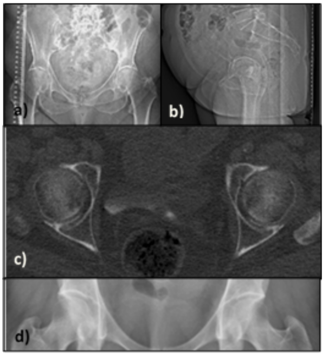

Different CT methods were evaluated: the topogram method, cross-sectional method, short-spiral method, standard-spiral method, and flash-spiral method. The topogram method contains a posteroanterior (PA) and a lateral topogram (Figure 3) when viewing the pelvis.12 The tube voltage was set to 100kV in both topograms while the tube current was 20mA in the PA topogram and 60mA in the lateral topogram. The cross-sectional method (Figure 3) contains the topogram method and two cross-sectional images of fovea caput.20 The parameters for this method were set to 14 quality reference effective mAs with automatic exposure control (AEC) activated, 1×5cm collimation and 120kV tube voltage. The short-spiral method contains the topogram method and spiral imaging which only includes the area around the head of femur (Figure 3). The standard -, and flash-spiral method contain only a PA topogram and spiral imaging of the pelvis including lumbar vertebra 5 to the ischial tuberosity. The flash scan uses two sets of X-ray tubes. The scanning parameters for the spiral methods are presented in Table 1. The CT images were reconstructed using iterative reconstruction (SAFIRE).

Figure 3 Images of topogram- (a, b) and cross-sectional (c) methods, together with the area of the short-spiral (d).